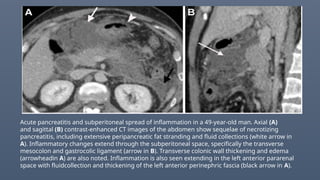

Acute pancreatitis and subperitoneal spread of inflammation in a 49-year-old man. Axial (A)

and sagittal (B) contrast-enhanced CT images of the abdomen show sequelae of necrotizing

pancreatitis, including extensive peripancreatic fat stranding and fluid collections (white arrow in

A). Inflammatory changes extend through the subperitoneal space, specifically the transverse

mesocolon and gastrocolic ligament (arrow in B). Transverse colonic wall thickening and edema

(arrowheadin A) are also noted. Inflammation is also seen extending in the left anterior pararenal

space with fluidcollection and thickening of the left anterior perinephric fascia (black arrow in A).